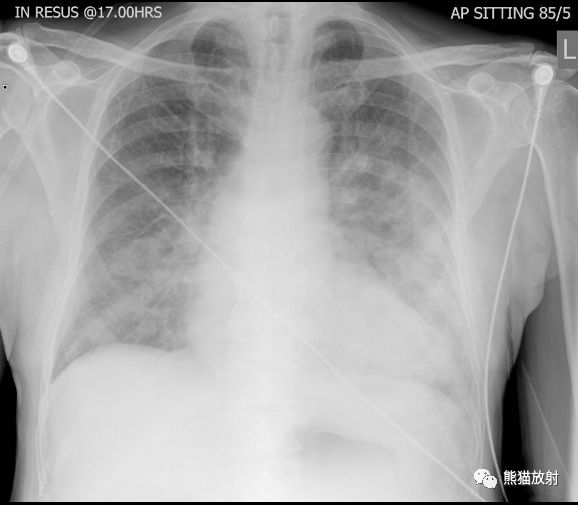

肺部之“蝙蝠翼征”

蝙蝠翼征 或 蝶翼征

蝙蝠翼样肺部影是指双侧肺门周围的阴影。

通常在正位胸片上用来描述相关表现,也可指胸部CT上的表现。